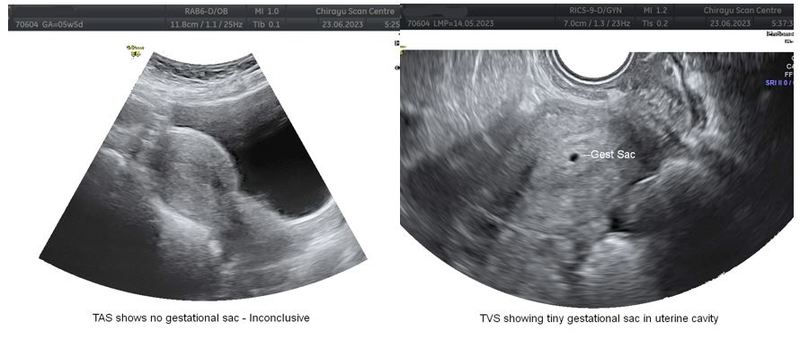

Case 1Mrs. X, 28Y/F G2, P1, L1 with amenorrhea of 40 days and +ve UPT, presented with bleeding p/v and mild cramping for one day. TAS showed an empty uterine cavity, normal adnexa, and no free fluid in POD. Here TAS is inconclusive with three possibilities – Early intra-uterine pregnancy, Complete abortion, or Ectopic gestation. Without TVS, the recommendation is to repeat the ultrasound in 1 week / SOS. TVS showed a tiny gestational sac measuring about 3mm in the uterine cavity, giving a definite diagnosis of early intra-uterine gestation.